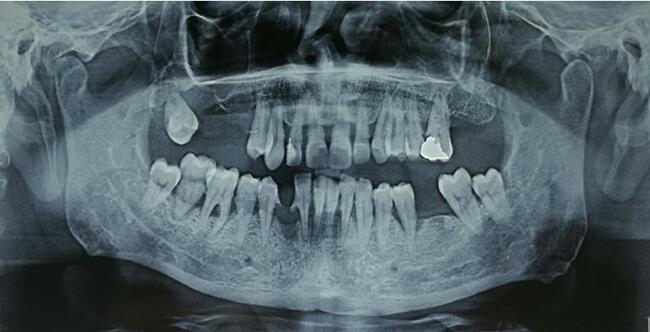

Panoramic radiograph demonstrated a relatively well-delineated osteolytic radiolucent lesion that extended from the upper right first premolar to the upper right third molar (between teeth 14 and 18) that had eroded the right maxillary sinus floor (Figure 1).

OCCs are depicted in CT scans as both well-defined and ill-defined tumors, causing cortical erosion and/or cancellous destruction of the adjacent bone while primarily affecting the soft tissues.4,7,11 MRI shows tumors of heterogeneous intensity, causing gingival inflammation but sparing the extrinsic muscles, when located at the tongue. Panoramic radiographs, used as a screening tool, usually reveal ill-defined, irregular osteolytic radiolucent lesions infiltrating the cortical and cancellous bone and involving anatomic structures, such as the nasal floor, sinus walls, or mandibular canal.5 In this case, the tumor had infiltrated not only the adjacent bone but also the right maxillary sinus floor, extending widely into the sinus.